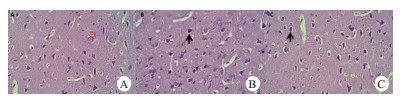

CPR后动物脑损伤明显,无论在光镜下受损神经元数,还是在电镜下线粒体超微结构受损评分均较假手术组差异有统计学意义(P<0.01,表 2)。经过丁苯酞治疗后,HE染色显示,丁苯酞组动物的大脑额叶皮质中央前回受损的神经元数与对照组相比显著降低(P<0.01,图 1);电镜下,丁苯酞组动物线粒体超微结构受损程度评分显著高于对照组(P<0.01,图 2)。与假手术组比较,对照组动物大脑额叶皮质神经细胞AI显著增加(P<0.05);对于经过丁苯酞治疗后,AI较对照组显著降低(P<0.05,图 3)

| 大脑额叶皮质中央前回受损神经元变化包括胞浆红染、Nissl体减少和核固缩(箭头所示)。假手术组(A)神经元基本正常,丁苯酞组(C)受损的神经元数显著低于对照组(B) 图 1 大脑额叶皮质中央前回组织病理学变化(HE×200) Fig 1 Histopathological changes in the central anterior gyrus of the cerebral frontal cortex(HE×200) |